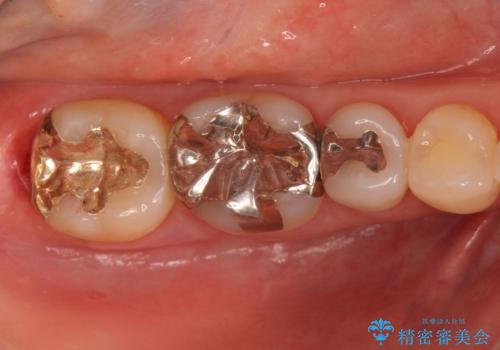

- 詰め物が外れたから作り直しをしたいとのことで来院されました。

外れた状態で日にちが経過していたため、まわりの歯ぐきが歯の上に乗っかっている状態です。

歯ぐきの形を整えてから治療をしていきます。